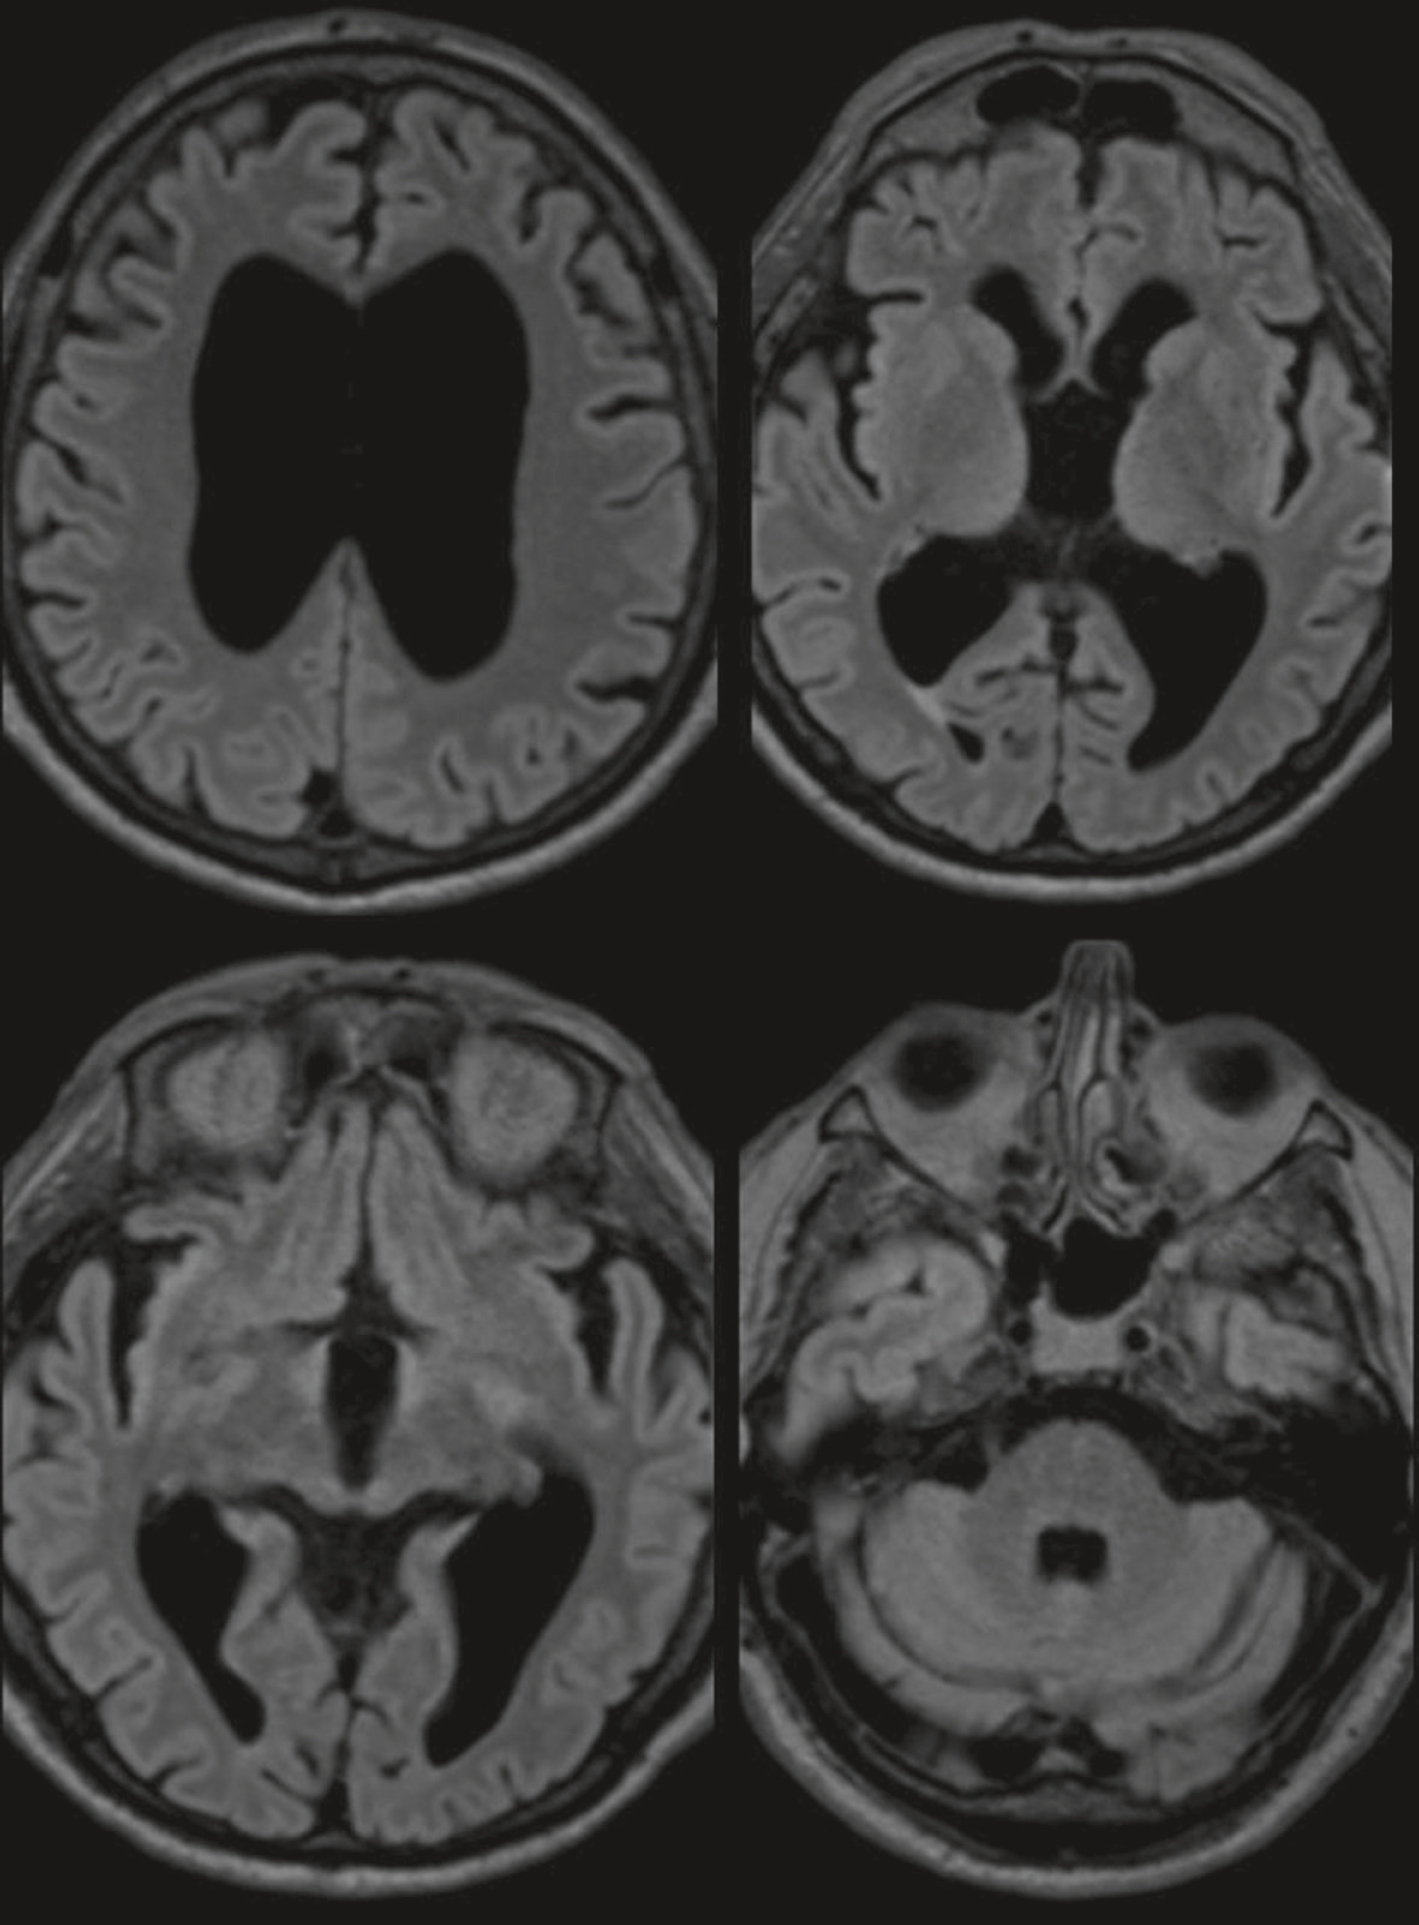

QRM 67

Vous voyez en consultation un patient de 72 ans qui vous est adressé pour des épisodes de chute à répétition. Il vous présente l’IRM cérébrale suivante réalisée en externe (fig. 32.4). Quels sont les signes cliniques classiques que peut présenter ce patient en rapport avec le diagnostic suspecté devant les données de l’imagerie ?

Série de quatre coupes axiales d’IRM cérébrale en séquence FLAIR montrant une atrophie cérébrale diffuse prédominante au niveau des ventricules latéraux et du cortex temporal. Les ventricules apparaissent très dilatés de manière symétrique, notamment les cornes frontales et occipitales, traduisant une ex-vacuo dilatation en lien avec une perte de volume cérébral. La largeur des sillons corticaux est augmentée, particulièrement marquée dans les régions pariétales et temporales, avec un effacement partiel de la substance blanche adjacente. Le cortex temporal médian présente des signes d’atrophie bilatérale, visibles par une amincissement et un élargissement des espaces péri-hippocampiques. L’aspect global évoque une encéphalopathie dégénérative, possiblement une maladie d’Alzheimer à un stade évolué. Aucun hypersignal parenchymateux focal, ni effet de masse ou signe d’œdème, n’est identifié sur les différentes coupes analysées.

- A 679une marche à petits pas

- B des céphalées chroniques

- C une démence de type frontale

- D un signe de Babinski bilatéral

- E une incontinence urinaire